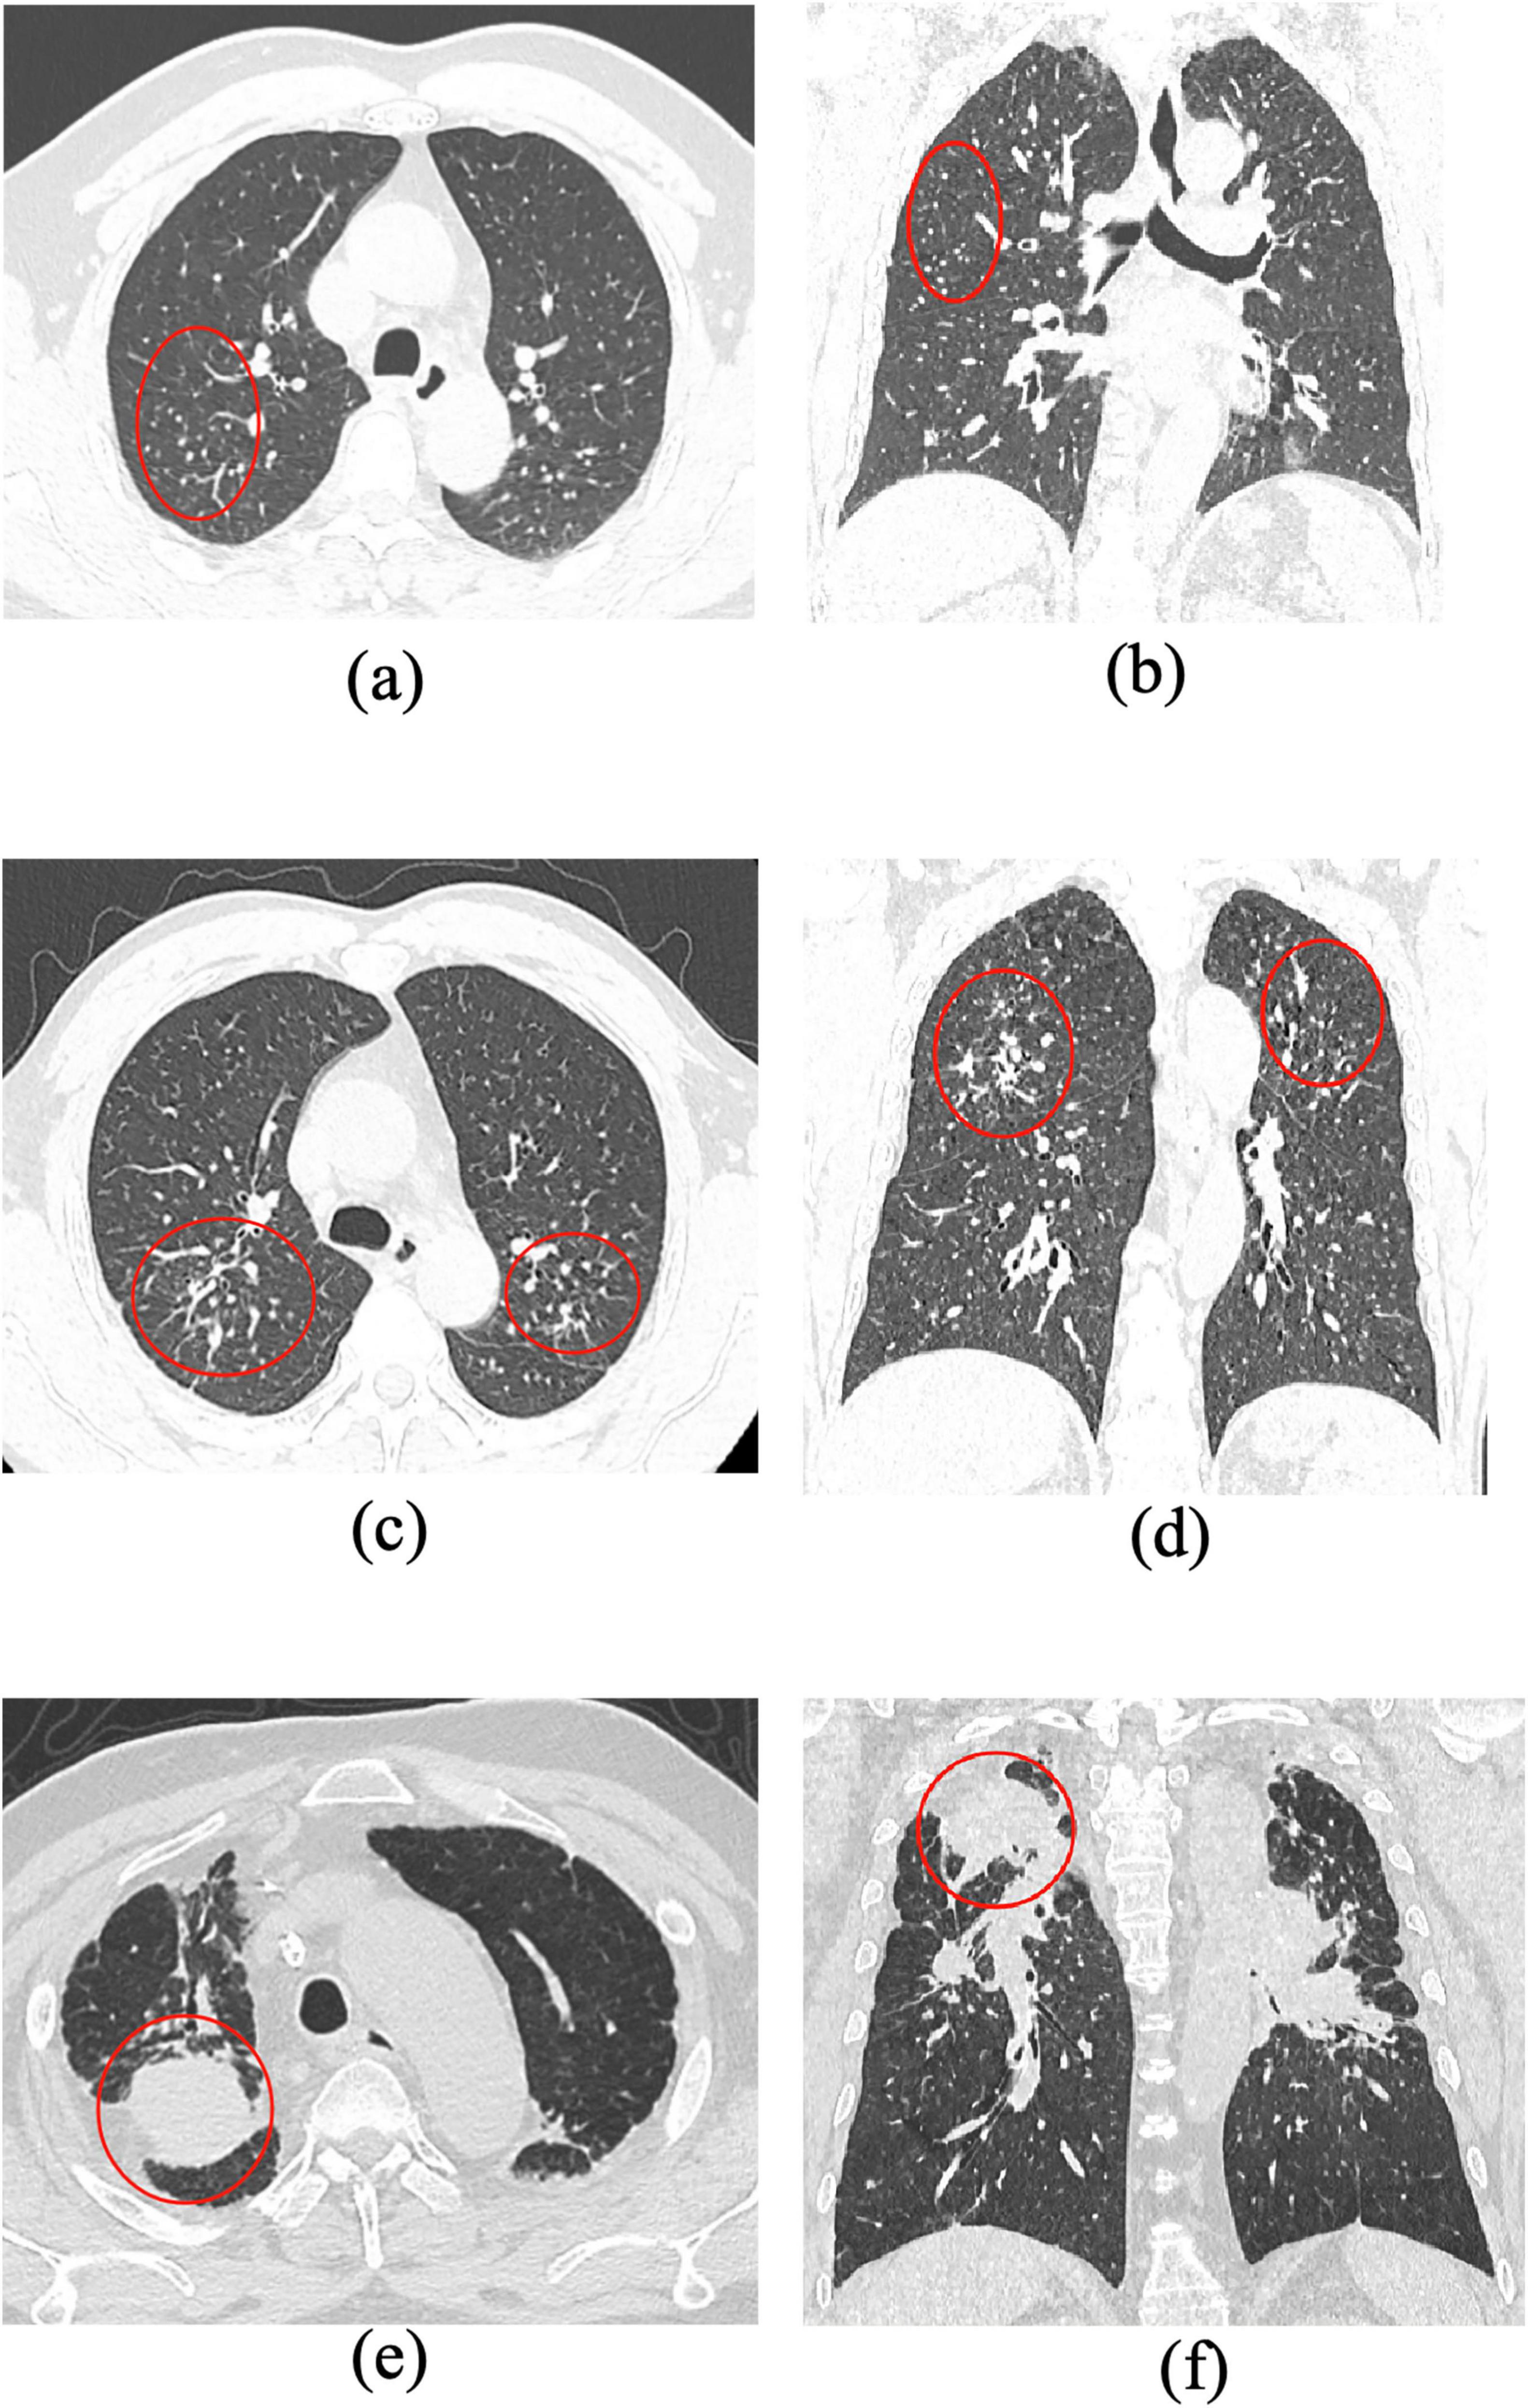

Supplementary Figure 1Representative CT images showing different stages of pneumoconiosis (axial and coronal views). (a,b) Axial and coronal chest CT images of a Stage I pneumoconiosis patient demonstrate multiple scattered, small, round, high-density nodules distributed in both lungs, predominantly in the right middle lung field. (c,d) Stage II pneumoconiosis is characterized by an increased number of small nodules and linear opacities, primarily clustered in the posterior segment of the right upper lobe. (e,f) Stage III pneumoconiosis exhibits more extensive and symmetrical large opacities (long diameter > 20 mm, short diameter > 10 mm) in the apical and posterior segments of both upper lobes. The lesions are accompanied by pleural thickening, traction, and partial calcification within the masses, along with multiple peripheral nodular opacities. Interpretation: as pneumoconiosis progresses from Stage I to Stage III, CT imaging reveals a gradual increase in nodule size and density, evolving into confluent fibrotic masses with pleural involvement and architectural distortion, consistent with advanced PMF.

Supplementary Figure 2CT imaging and immunohistochemical (IHC) profiles of different histological types of lung cancer. (a,b) Axial and coronal CT images of squamous cell carcinoma in the left upper lobe reveal a soft-tissue mass located in the anterior segment, exhibiting short spiculation and well-defined margins. IHC profile: CK (+), CK7(+), CK5/6(few +), TTF-1(−), NapsinA(−), CgA(−), Syn(−), P40(+), P63(+), CDX-2(−), CK20(−), Ki-67 (∼80% +), Villin(−). Diagnosis: Squamous cell carcinoma of the lung. (c) Axial CT image of poorly differentiated adenocarcinoma in the right middle lobe shows an ill-defined mass with partial truncation of the middle bronchus. IHC profile: CK (+), CK7(+), TTF-1(+), NapsinA(−), CgA(−), Syn(−), CD56(−), INSM-1(+), CK5/6(−), P40(−), P63(−), Ki-67 (∼70% +). Diagnosis: Poorly differentiated adenocarcinoma. (d) Axial CT image of a poorly differentiated small cell carcinoma in the right lower lobe demonstrates a large, irregular mass with unclear margins, bronchial obstruction, and significant mass effect. IHC profile: CK (+), Ki-67 (∼60% +), CK7(+), P63(−), P40(−), TTF-1(−), NapsinA(−), Syn(weak +), CgA(−), CK5/6(weak +), INSM-1(−), CD56(weak +), HMB-45(−), LCA(−), INI-1(+), S100(−), NUT(−), CD20(−). Diagnosis: Poorly differentiated small cell carcinoma confirmed by immunohistochemistry. Interpretation: Distinct CT and immunohistochemical patterns are evident among different lung cancer subtypes. While squamous cell carcinoma typically presents as a well-circumscribed lesion with peripheral spiculation, adenocarcinoma and small cell carcinoma often exhibit irregular borders, bronchial involvement, and aggressive radiologic behavior. Combined radiologic and IHC assessment remains essential for accurate histopathological classification.